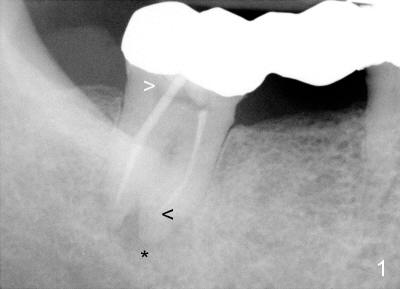

In fact, the retainer is separated from #32 abutment when the FPD is being sectioned between #30 retainer and #31pontic. The mesiobuccal open margin of the tooth #32 is evident (Fig.2,3 yellow <). It appears that the crown was seated on the composite-like material, instead of sound tooth structure. There is void around the post (Fig.2 white >). Furthermore, the mesial canal seems to be not well condensed (curved void, Fig.2 black <).

The void in the mesial root turns out to be a missing mesiobuccal canal (Fig.4,5 black <). Initially, RCT filling material is difficult to remove from apical portion of the distal and mesiolingual canals (Fig.4 white >), while the apical portion of the mesiobuccal canal is obliterated.